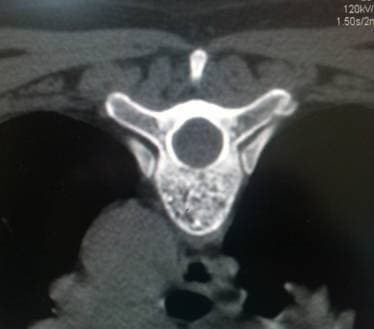

Гемангиома тела позвонка

Ячеистая структура тела позвонка при гемангиоме

Структура "пчелиные соты" при гемангиоме